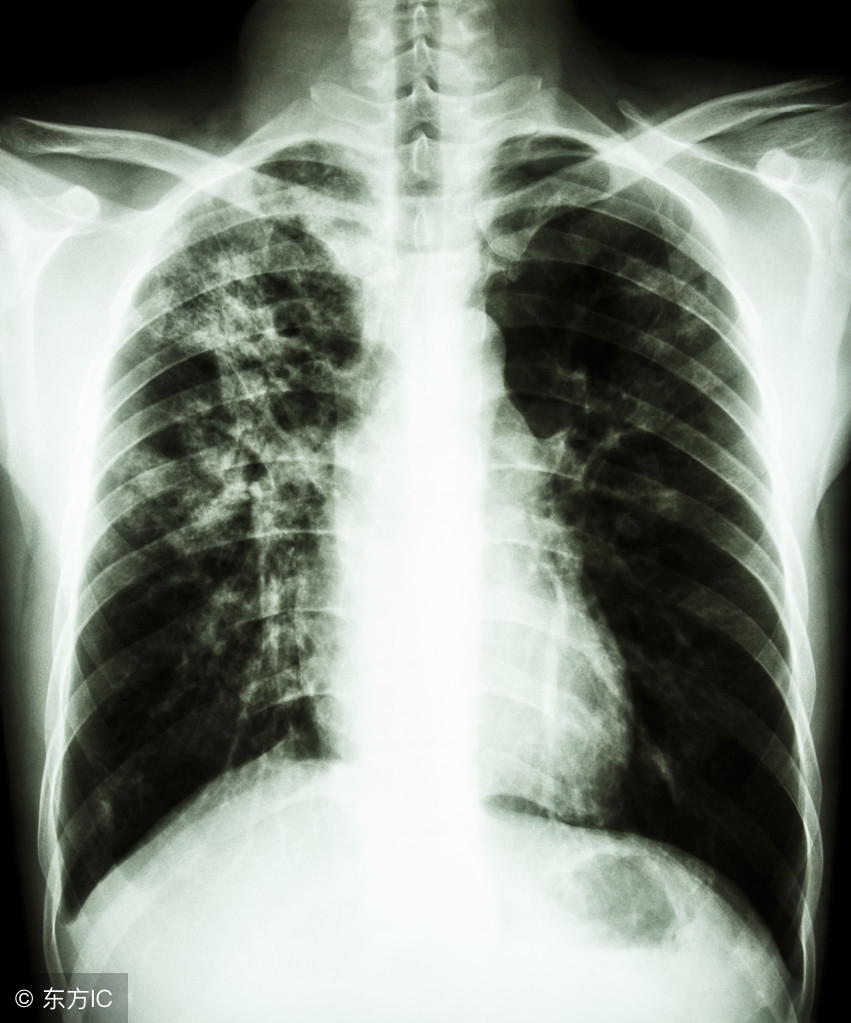

3.肺结核的主要症状

很多肺结核患者会出现长期咳嗽、咯痰,甚至痰中带血,咯血等症状,部分患者有胸痛、呼吸困难等症状。除此之外,发热也是最常见症状,主要表现为潮热、盗汗,身体消瘦,食欲减退等。